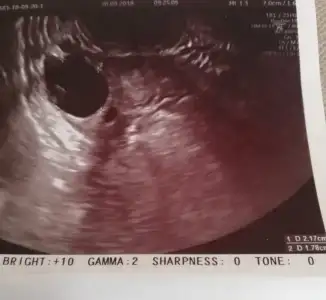

whiterabbit88 Kızlar Bn şimdi çıktım doktordan eve geldim çok şükür rabbim e yumurtacıklarıma birsey olmamış ikiside daha da büyüdü bi günde eridim bittim sandım Ordada tutamadım kendimi doktor iğne için mi geldin dedi hadı yap gel konuşalım dedi yok dedim önce konuşalım odaya girmemle ağlamam bir oldu anlattım hemen baktı birsey yok sakin ol bak daha da büyümüşler Bn onları şimdi çatlatıcam dedi.. Bana senı çok iyi görmüştüm ve çokta umutluyum ne olur stresi Bı kenara koy ve mutlu olmaya bak... Senin mutlu iyi hissetmen bu ilaçlardan da daha etkili ve önemli unutma dedi... Doktor çok üzüldü Bnim halime iğneyi bile normalde acilde özel hastane ücret alır öyle yaparlar hemşireye rica edip arayıp getirdi hemsirede hamileydi inş uğur getirir dedi..